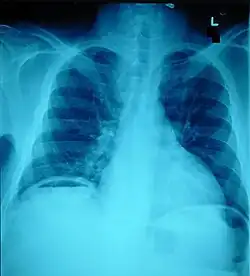

Pneumoperitoneum, seen as an air bubble on the lower left side of the X-ray film

The small intestine takes up a large part of the abdomen and is likely to be damaged in penetrating injury.[5] The bowel may be perforated.[4] Gas within the abdominal cavity seen on CT is understood to be a diagnostic sign of bowel perforation; however intra-abdominal air can also be caused by pneumothorax (air in the pleural cavity outside the lungs that has escaped from the respiratory system) or pneumomediastinum (air in the mediastinum, the center of the chest cavity).[4] The injury may not be detected on CT.[4] Bowel injury may be associated with complications such as infection, abscess, bowel obstruction, and the formation of a fistula.[4] Bowel perforation requires surgery.[4]

Ten percent of people with polytrauma who had no signs of abdominal injury did have evidence of such injuries using radiological imaging.[1] Diagnostic techniques used include CT scanning, ultrasound,[1] and X-ray.[7] X-ray can help determine the path of a penetrating object and locate any foreign matter left in the wound, but may not be helpful in blunt trauma.[7] Diagnostic laparoscopy or exploratory laparotomy may also be performed if other diagnostic methods do not yield conclusive results.[5]